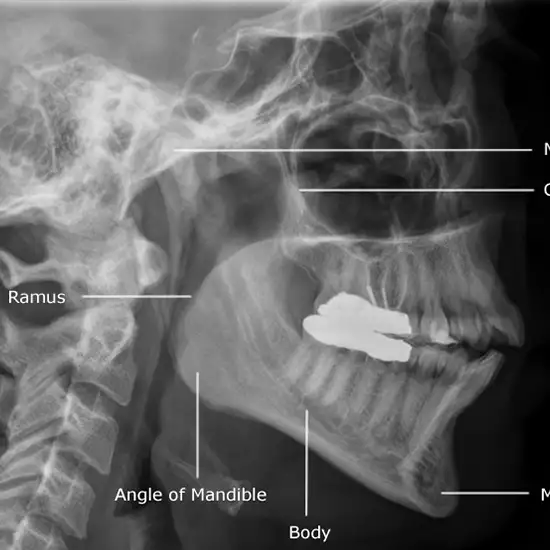

The maxilla is the bone responsible for forming the upper jaw. A Maxilla Lateral View (upper jaw) X-ray examination is performed to view the maxillary bones. The two maxillary bones on each side of the face meet at the midline and in the center part of the face.